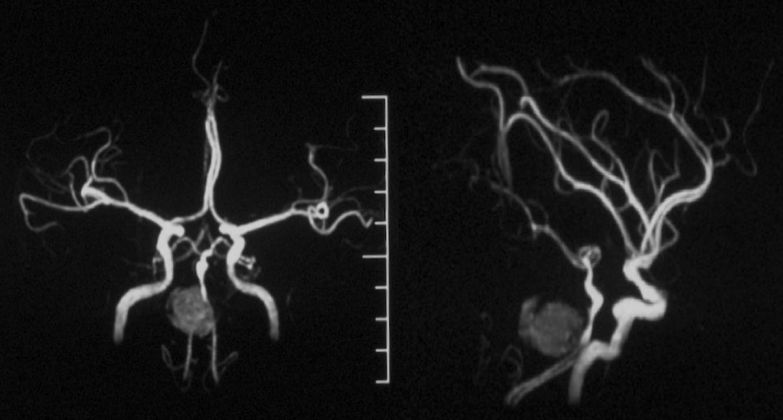

本院DSA:基底动脉巨大夹层动脉瘤,双侧后交通动脉未见明显开放(图6)。

图6

本院 DSA三维血管重建(2019-10-10)显示:基底动脉巨大夹层动脉瘤(图7)。

图7

2、头部核磁共振显示:脑干占位性病变,边界较清晰,较大层面大小约35 mmx25 mm。MRA显示:基底动脉夹层动脉瘤。DSA显示,基底动脉巨大夹层动脉瘤,最大长径为:10.8 mm,最大短径为3.2 mm。根据患者症状及影像学诊断,基底动脉巨大夹层动脉瘤进行性增大压迫脑干,不排除脑干水肿可能,亟待手术治疗。

3、由于双侧后交通动脉未见明显开放,为保证脑干血供,手术必须确保载瘤动脉通。动脉瘤累及左侧AICA,基底动脉穿支丰富,位置深在,而且动脉瘤为夹层动脉瘤开颅手术治疗困难,且风险极高。回顾文献及本中心治疗经验,此类动脉瘤血流导向装置疗效较好,经科内讨论后决定运用Tubridge血流导向装置治疗。